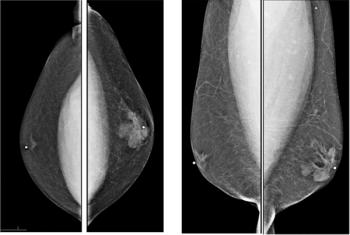

A 55-year-old female found to have a cardiac mass during evaluation of dizziness. Cardiac CT showed lesion of soft tissue density confined in right atrium.